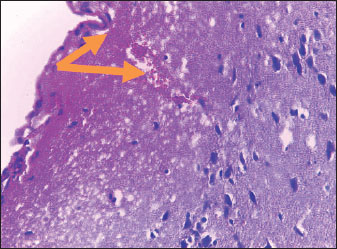

Brain of control group appeared normal structure of tissue with manifestation of Purkenji cells (Fig. 1), whereas sodium benzoate administration at low dose (200 mg/kg) occurred several histological lesions as hypertrophy of neurons (Fig. 2), pair nuclei arranged encompassed with clear space (Fig. 3), bleeding with degeneration of nerve cells (Figs. 4 and 5), respectively. In addition, lesions such as vacuolation, congestion, and accumulation of inflammatory cells were also evident (Figs. 6 and 7). However, severe histopathological lesions were observed following high-dose of sodium benzoate exposure, such as degeneration of neurons stained in dark blue (Fig. 8), prominent vascular duct with inflammation (Fig. 9), vacuolation, edema, and clear congestion as seen in Figures 1012, respectively.

Fig. 6. Points to the brain of sodium benzoate group (200 mg/kg): vacuolation of neurons (H&E) (100×).

Fig. 7. Points to the brain of sodium benzoate group (200 mg/kg): vacuolation of neurons (H&E) (100×).

The histopathological lesions observed in the brain can be associated with two doses of sodium benzoate that cause defects in brain architecture. This agrees with the findings of Al-Ameen et al. (2022), who pointed to brain damage in the cortex, such as vacuolation, satellitosis, edema, and focal gliosis. The same study also described mild to severe changes according to the sodium benzoate ingestion dose. Similarly, a previous study by Mohammed and Al-Gnami (2022) referred to the passive histological effects of sodium benzoate in many tissues, causing vacuolation, degeneration, and infiltration of inflammatory cells. Furthermore, histopathological lesions may be due to DNA damage of neurons by sodium benzoate exposure. This is similar to the findings of Mohiuddin et al. (2022), who showed DNA fragments of rats treated with a high dose (120 mg/kg) of sodium benzoate.

The structural damage to the brain may be correlated with oxidative stress induced by sodium benzoate intake and the smashing of nucleic acids by reactive oxygen species, which are considered responsible for nervous changes. Khan et al. (2022) reported oxidative stress and toxicological impacts in rats treated with sodium benzoate. This is consistent with the findings of Cantuti et al. (2000) who viewed neurodegenerative flaws and, morphological and functional malformations in the brain caused by oxidative stress. Al-Badry (2024) also linked the adverse histological lesions and physiological changes to lipid peroxidation that resulted from the intake of Puma supplements. Excessive oxidation damage causes loss of cell functionality, resulting in cell death. Sabour and Ibrahim (2019) mentioned Similarly, mentioned oxidative stress elevation in erythrocytes of rat exposed to different doses of sodium benzoate . The pathological changes recorded in the current results following sodium benzoate administration may be associated with the effects of free free radicals that cause the breakdown of polyunsaturated in the membranes of cells, leading to functional disorders. Furthermore, Al-Badry (2023) demonstrated that the brain was histologically affected by topiramate exposure.